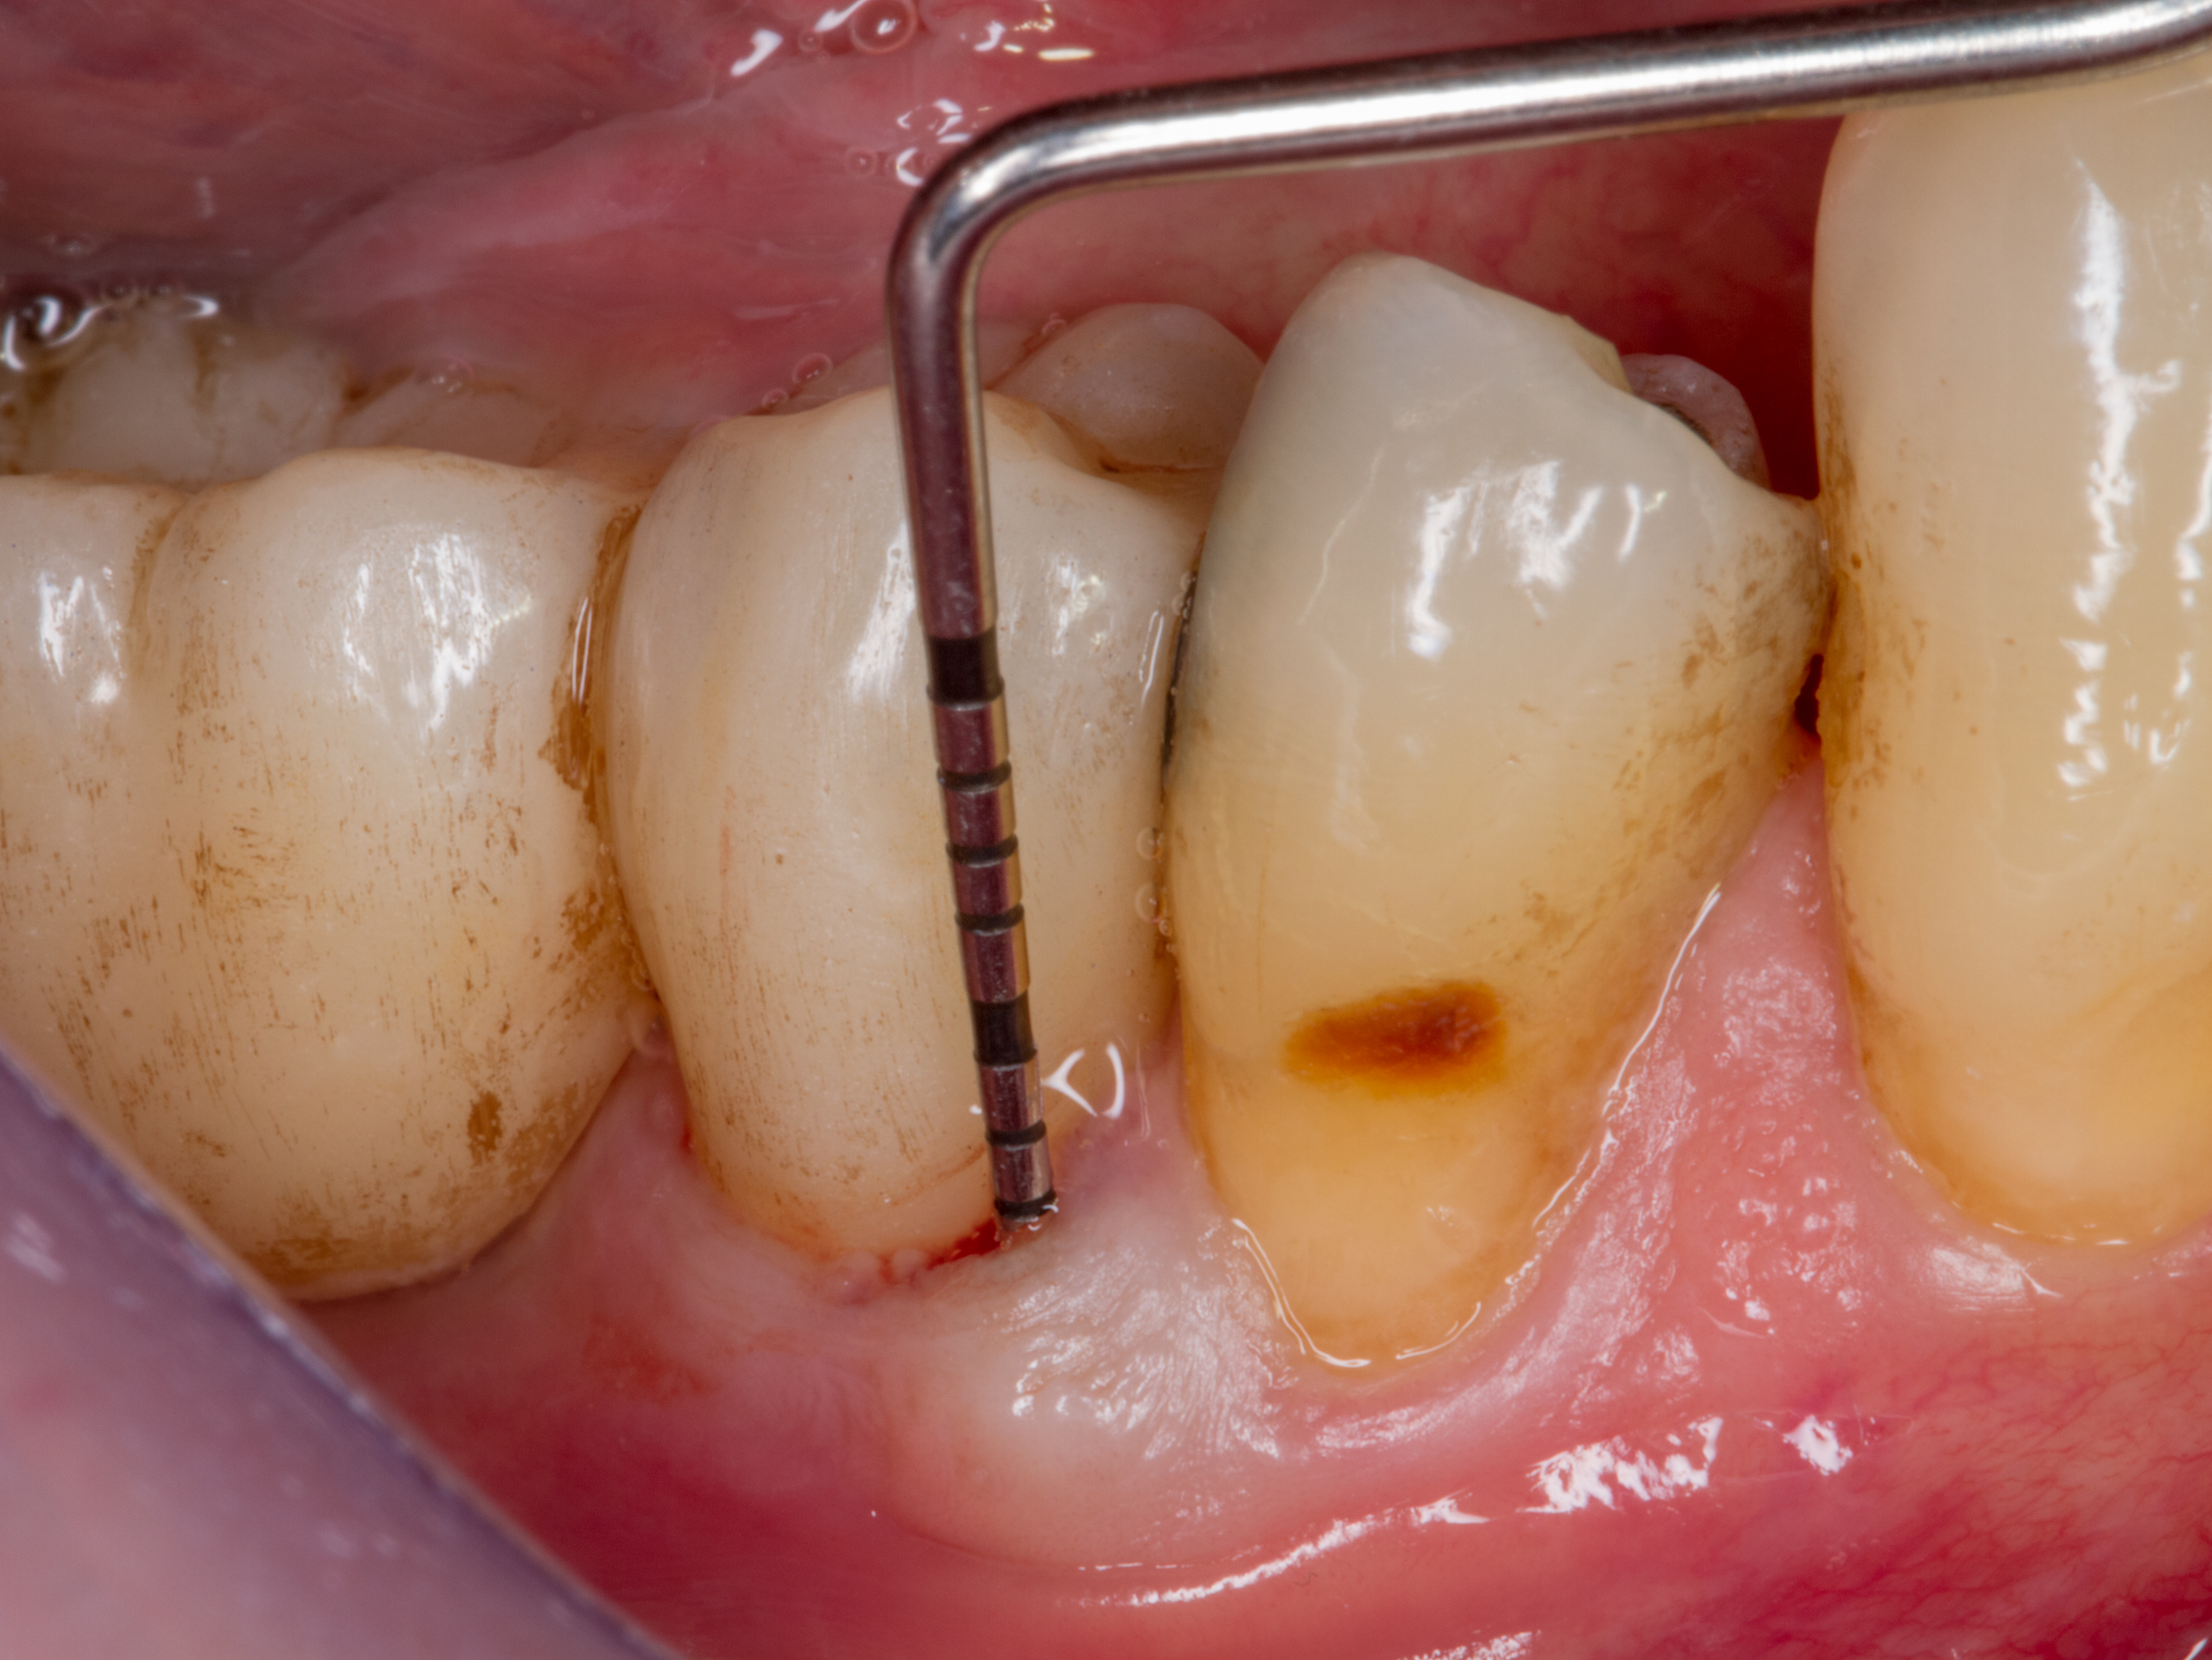

Il paziente si presenta alla nostra osservazione con l’elemento dentale 4.5 fratturato in senso verticale.

La situazione clinica appare essere la seguente: 4.5 elemento di ponte protesico con 4.6 in estensione, presenza di fistola vestibolare, sondaggio di 7 mm mesiale a radice di 4.5 fratturata con fuoriuscita ematica e purulenta (Figure 3-4).

Si effettua un bone mapping con la sonda parodontale per valutare la perdita di sostanza ossea della parete vestibolare. L’entità del difetto osseo è di circa 8 mm in senso corono-apicale per 5 mm in senso mesio-distale.